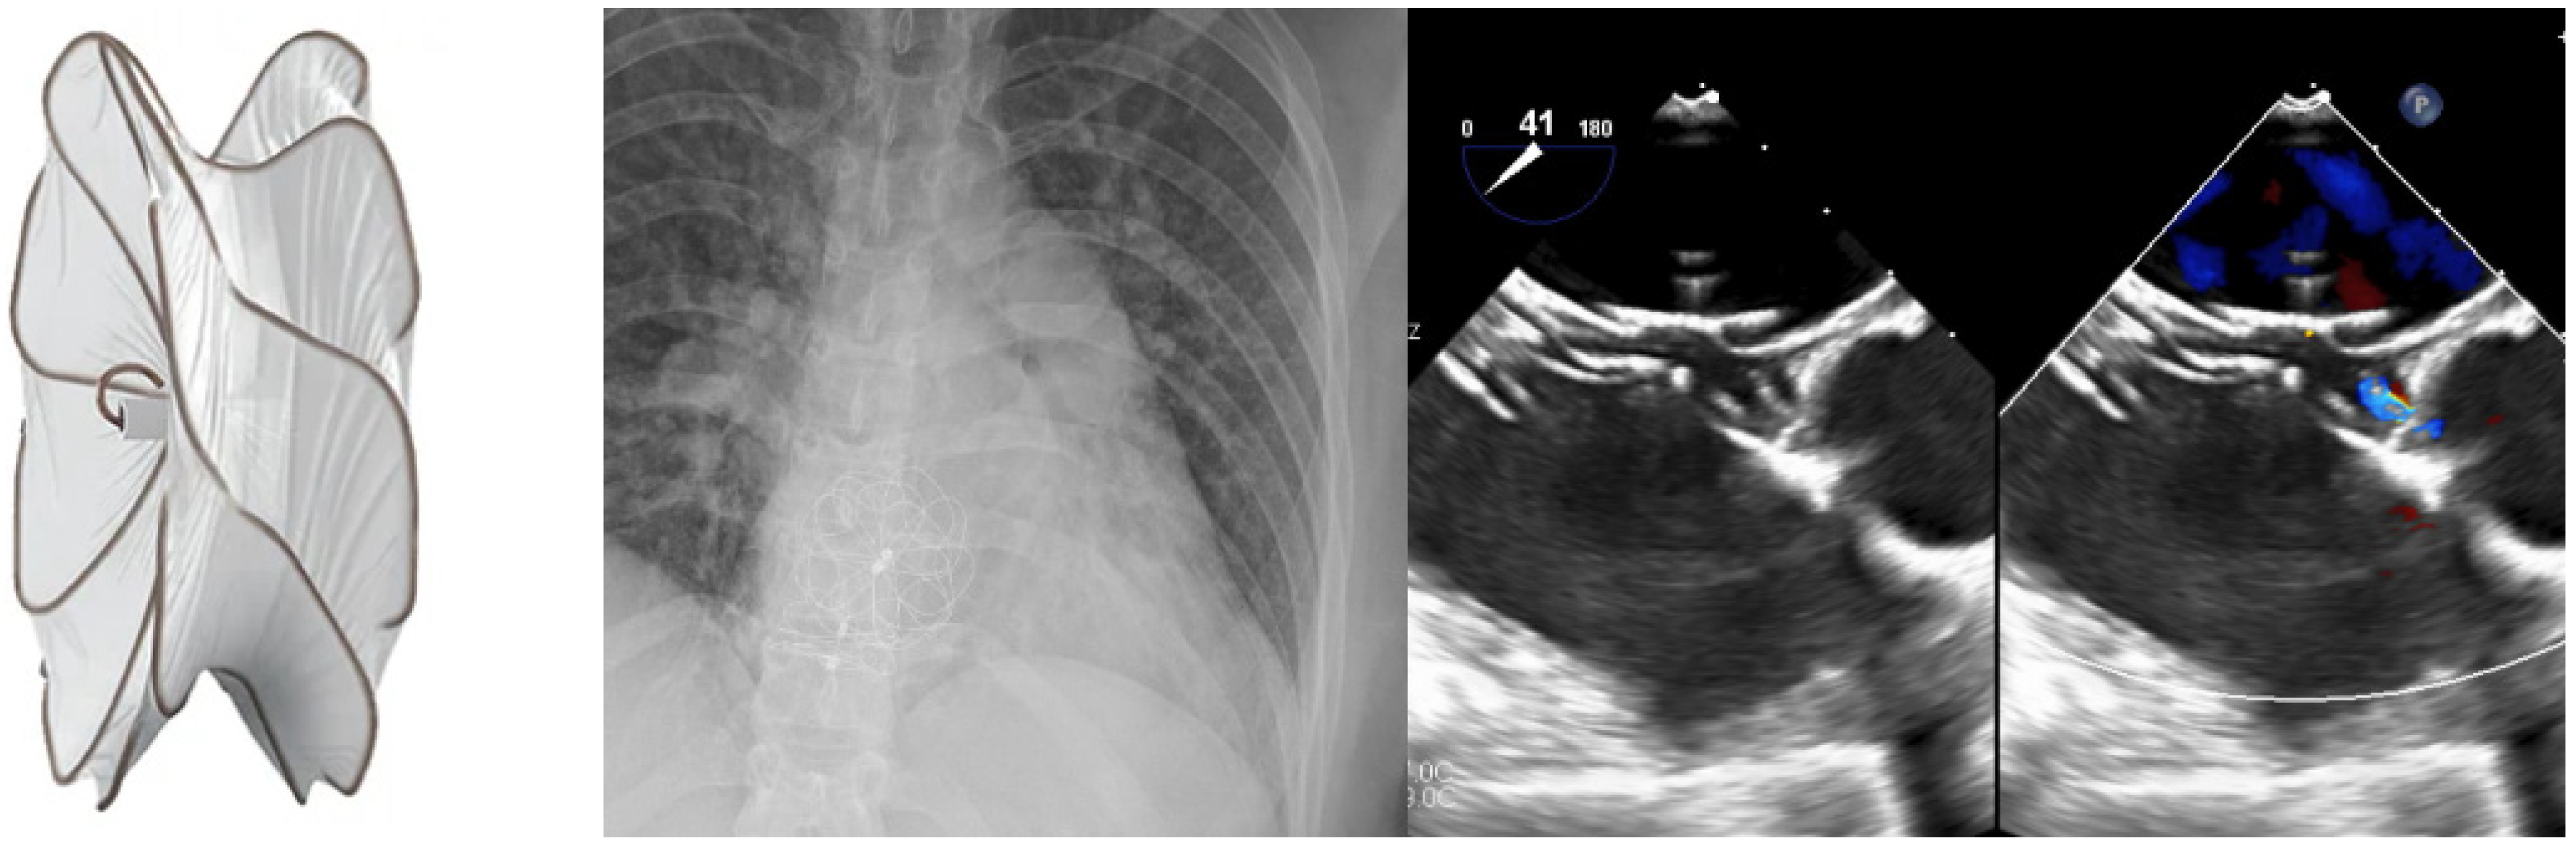

3. Secundum ASD Device Fenestration/Atrial Flow Regulator for Elevated Left Atrial Pressure

5. VSD Closure